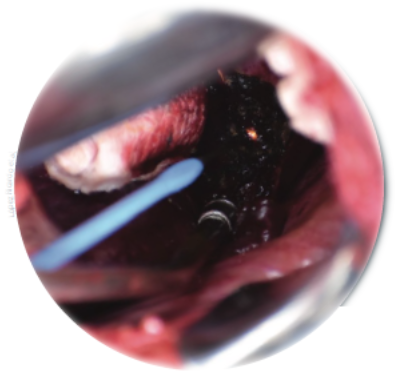

Figura 5 a) Se diseca triángulo hepatocístico de manera roma, se logra identificar arteria y conducto cístico, ambos de 2 mm de diámetro. b) Colocación de seda en arteria y conducto cístico. c) Se cortan ambas estructuras observándose ambos muñones sin fuga.